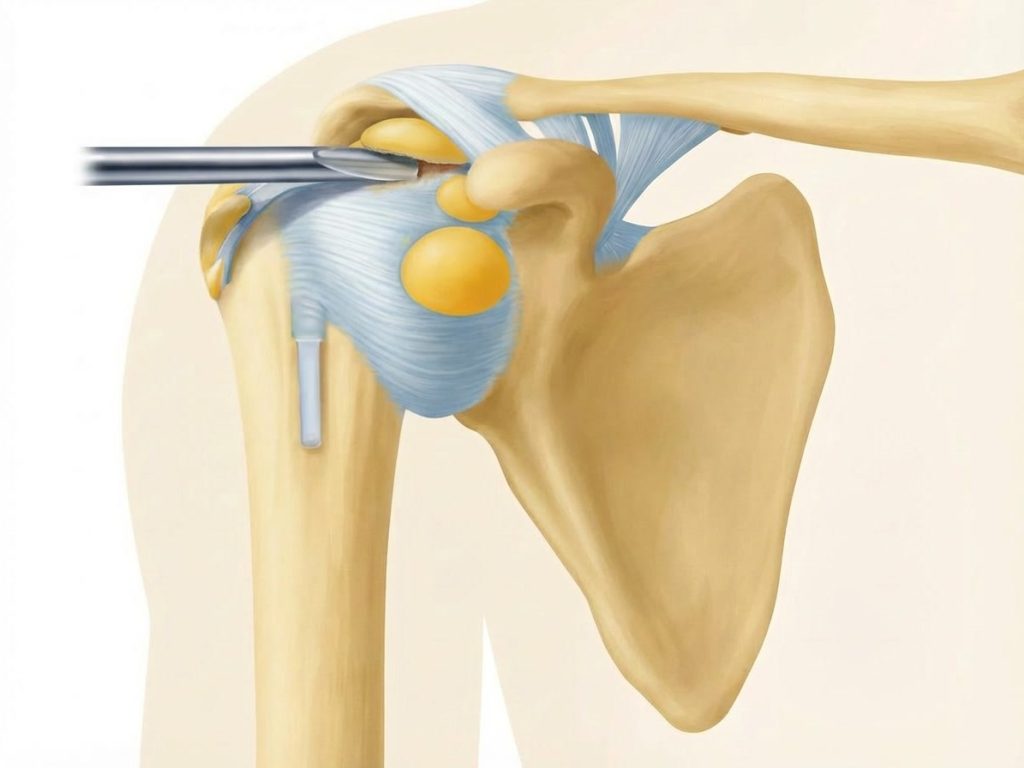

Schleimbeutel Schulter | Orthopäde 1010 | Dr. Ewald Timmel

Zugang

• Einführung der Arthroskopkamera über den hinteren (posterioren) Zugang). Anlage eines weiteren seitlichen (lateralen) Portales.

• Inspektion des Glenohumeralgelenks und des Subakromialraums, des Schleimbeutel und der Rotatorenmanschette

Darstellung des Subacromialraumes

• Die Kamera wird in den subacromialen Raum vorgeschoben.

• Der oft entzündete Schleimbeutel (Bursa subacromialis) wird entfernt (Bursektomie), um Platz zu schaffen und die Sicht zu verbessern.

Dekompression

• Mit einer Fräse oder einem Shaver wird das  Akromion Schulterdach von innen geglättet (Akromioplastik).

• Gegebenenfalls wird auch das Coracoakromialband teilweise gespalten, um zusätzlichen Raum zu gewinnen.

Ziel: Erweiterung des subakromialen Gleitraums für die Sehnen.